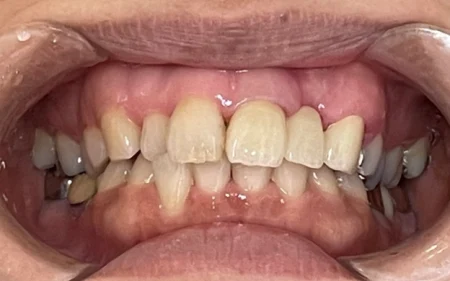

歯ぐきとポンティックが密着し、隙間がなくなったため、しっかり発音ができるようになりました。

患者様からは「隙間がなくなり息が漏れなくなったので、何も気にせず話せるようになった」と大変ご満足いただけました。

現在、ブリッジは問題なくお使いいただき、発音障害もみられません。

継続して定期検診にご通院いただいております。